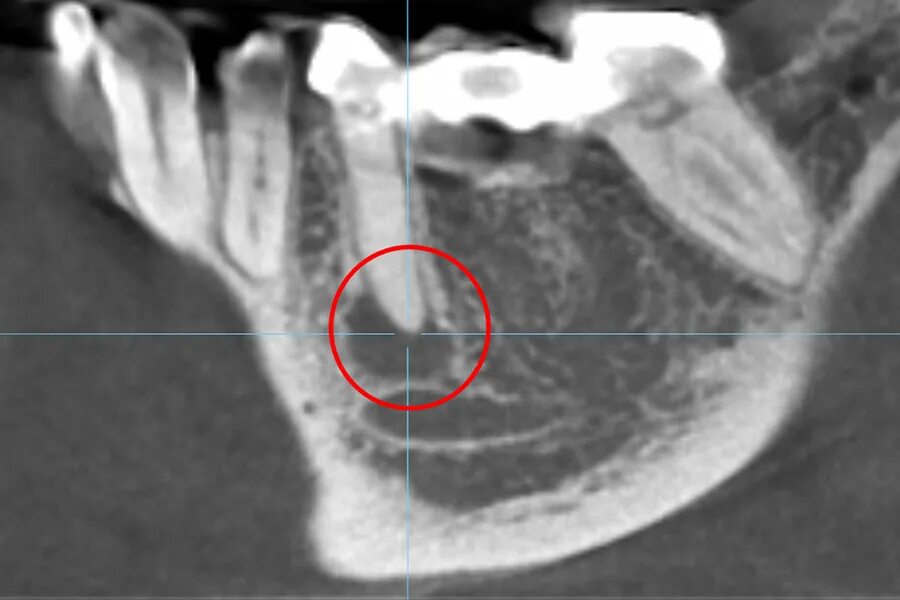

Резорбция ткани